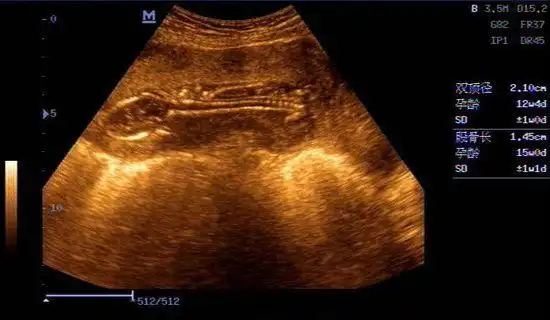

15周大的胎儿b超影像